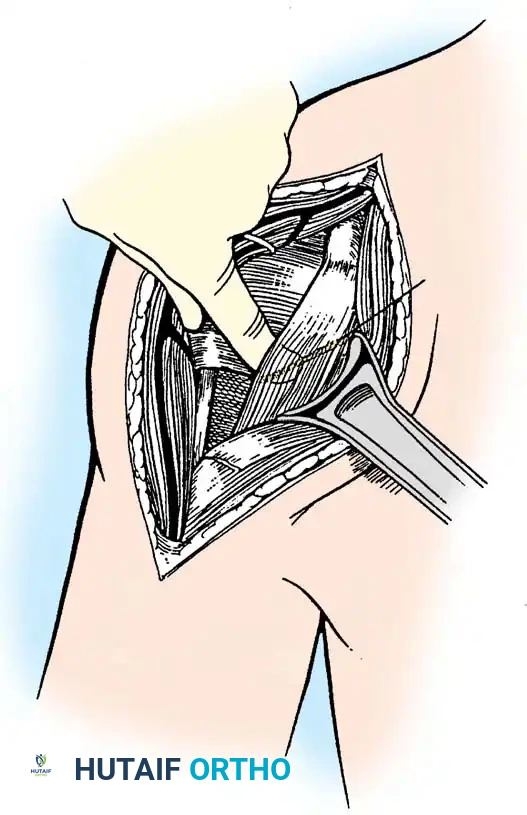

2. Subscapularis Management

The subscapularis is the gatekeeper to the joint. It can be managed via a tenotomy (1 cm medial to the lesser tuberosity), a lesser tuberosity osteotomy (LTO), or a subscapularis peel. LTO provides superior bone-to-bone healing and is increasingly favored.

Securely repair the subscapularis using heavy non-absorbable sutures through transosseous tunnels.